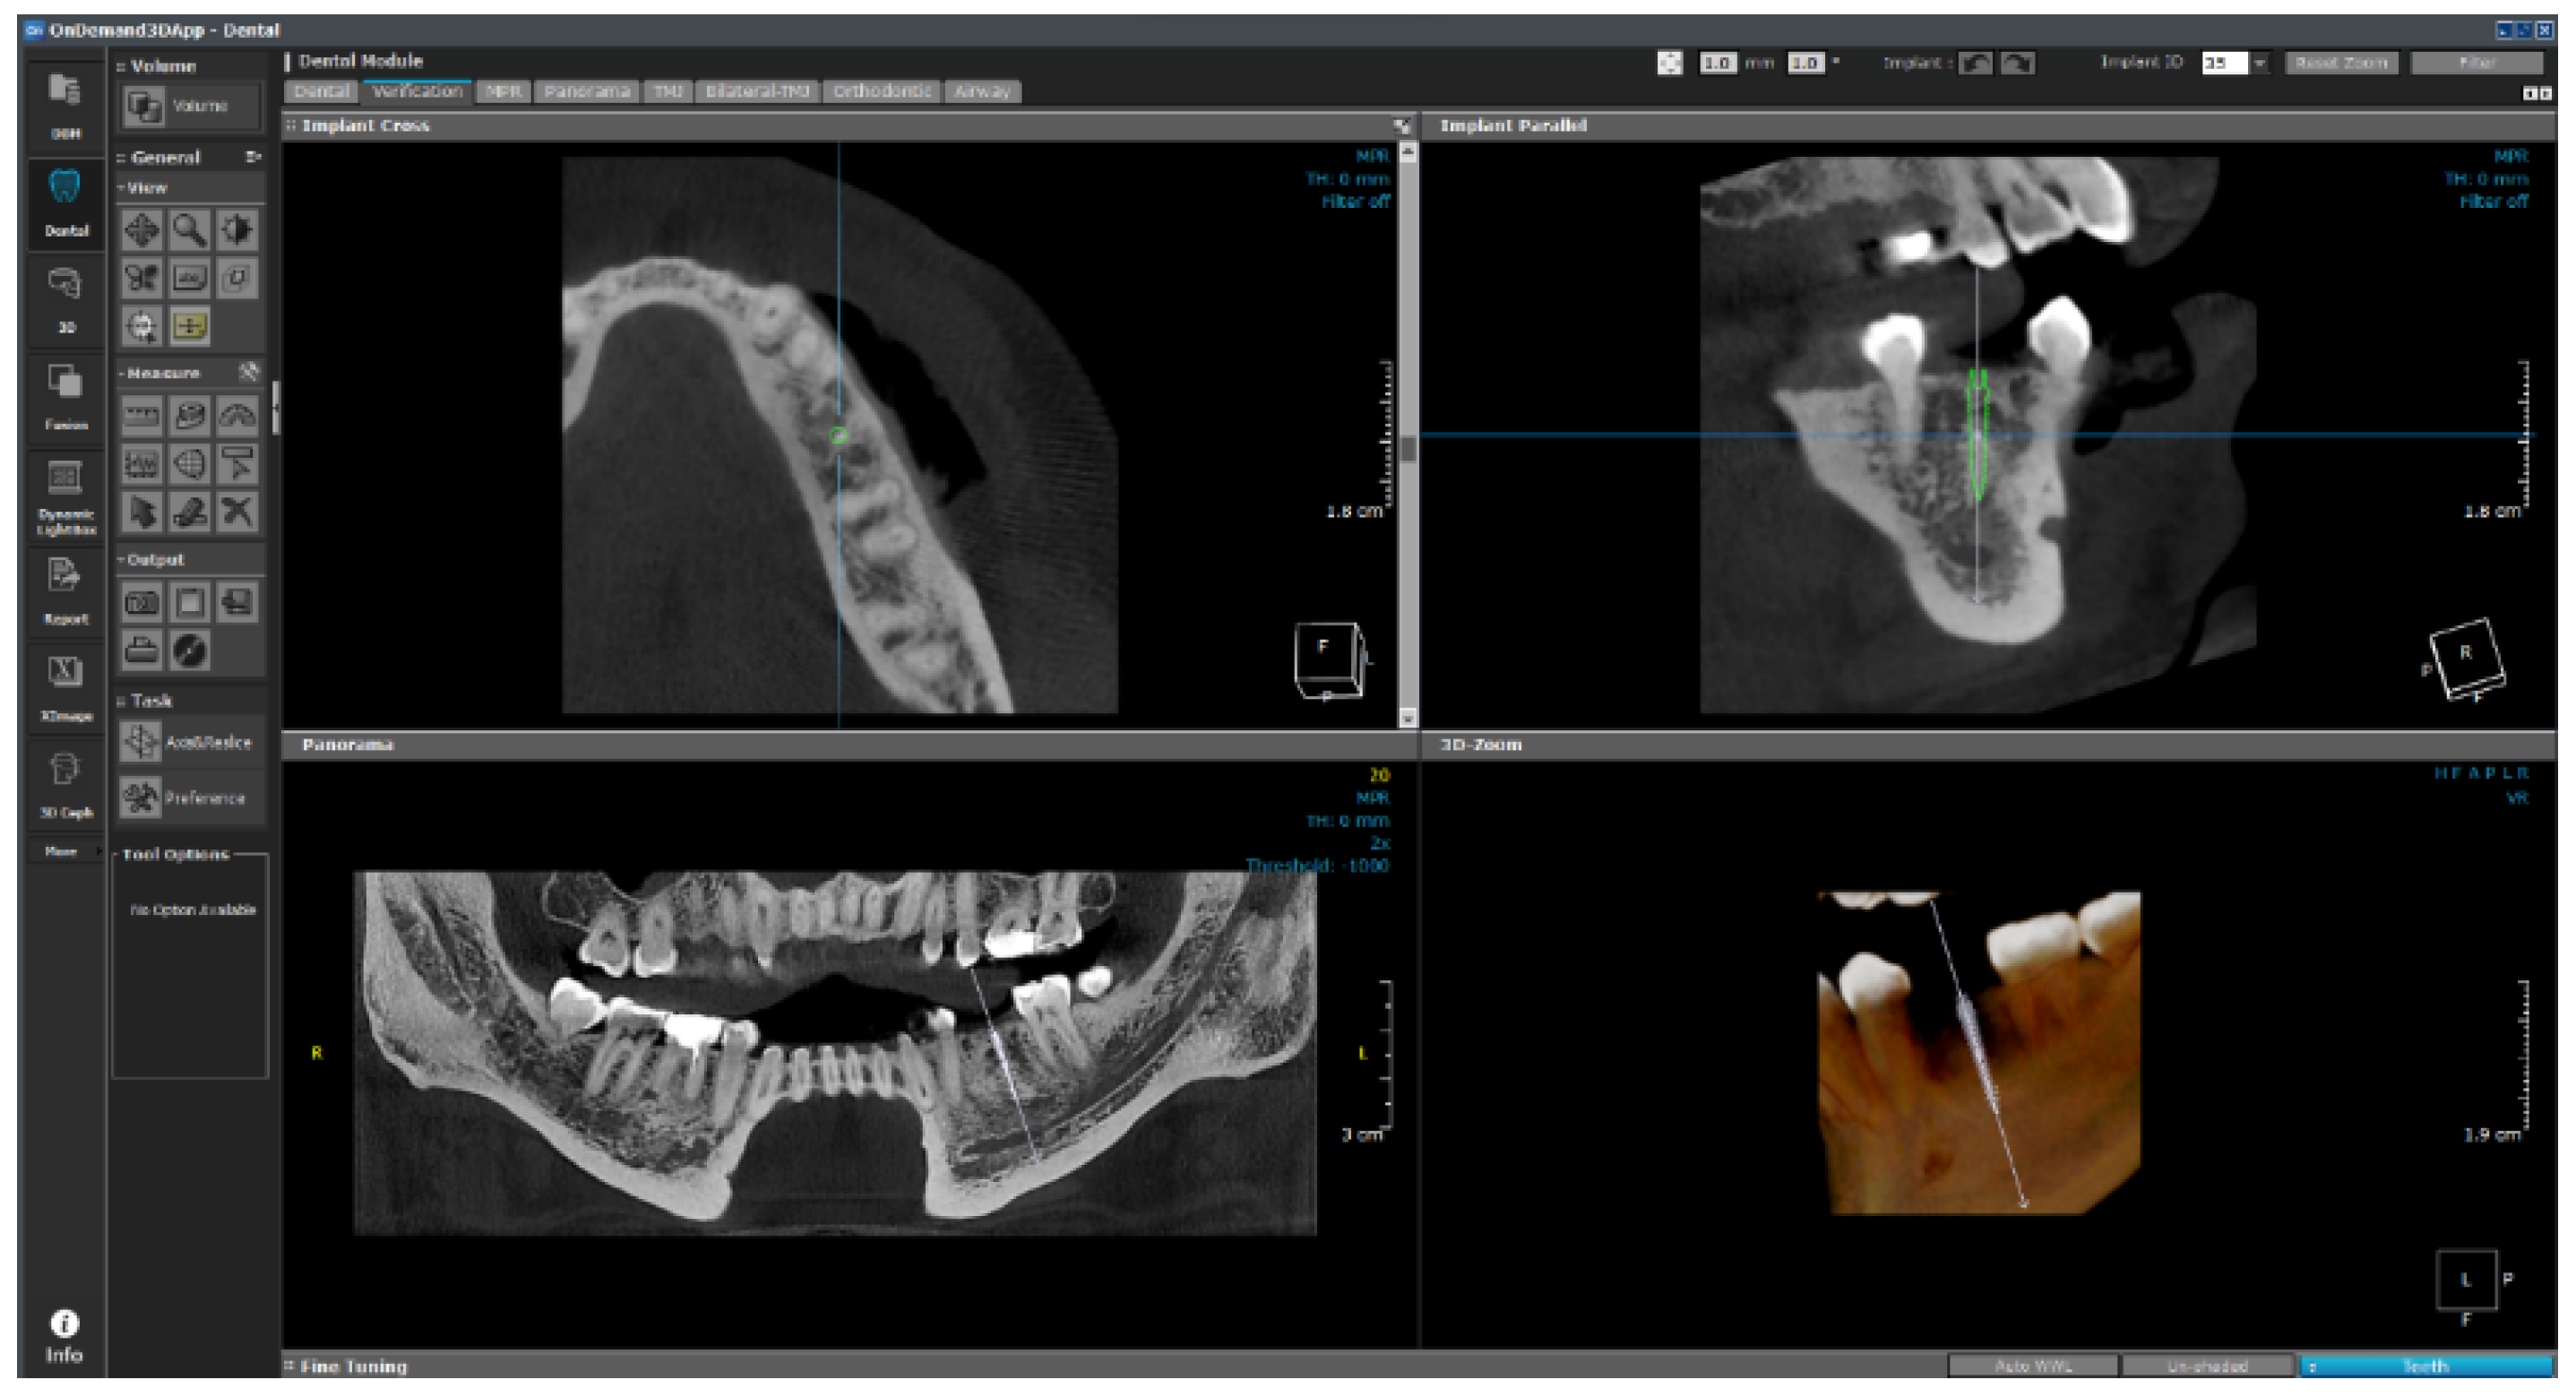

The software consists of modules such as demineralized bone matrix, Dental, 3D, 3D Cephalometric, Fusion, Dynamic LightBox, Report, Xlmage, and In2Guide, and each module functions independently. The dental module applied in this study is the standard for 3D dental reconstruction. This module contains eight different layouts, including dental, verification, multiplanar reformation (MPR), panorama, temporomandibular joint (TMJ), bilateral-TMJ, orthodontic, and airway. As shown in Figure 24, implant surgery can now be fully simulated using the dental module with the help of our real-size library of implant fixtures and abutments as well as the intra-oral/3D model scan data alignment function.

This module plays an auxiliary role for the user by integrating the implant ROM model to provide additional information. All necessary parameters from the implant ROM can be obtained from this module. As shown in Figure 25, the implant to be used is selected from the implant library by selecting the location of the tooth to be installed. Based on the selected location, appropriate bone material property values can be obtained, as shown in Figure 26.

As shown in Figure 27, the empty space between the teeth is determined from the photographic data, and the implant is placed. The six variables are subsequently changed, as shown in Figure 28, and are input in the 1-D CAE solver for automatic calculation. The stress level in the cortical bone is displayed in green for under 40 MPa and in red for higher.

Figure 24. Layout of the dental module.